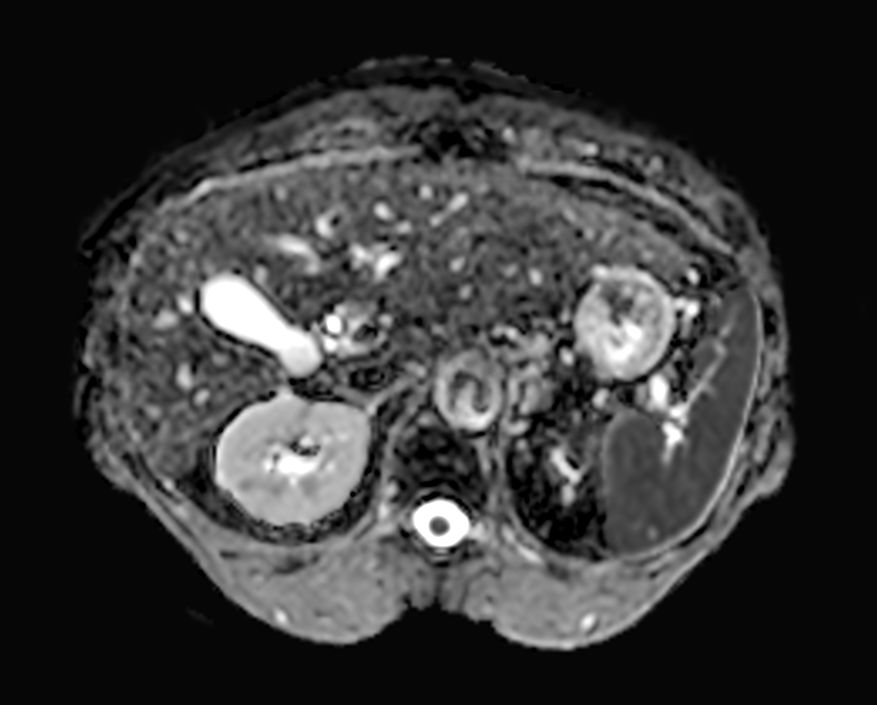

Diffusion (b0)

-

Diffusion (b1000)

Diffusion (ADC)